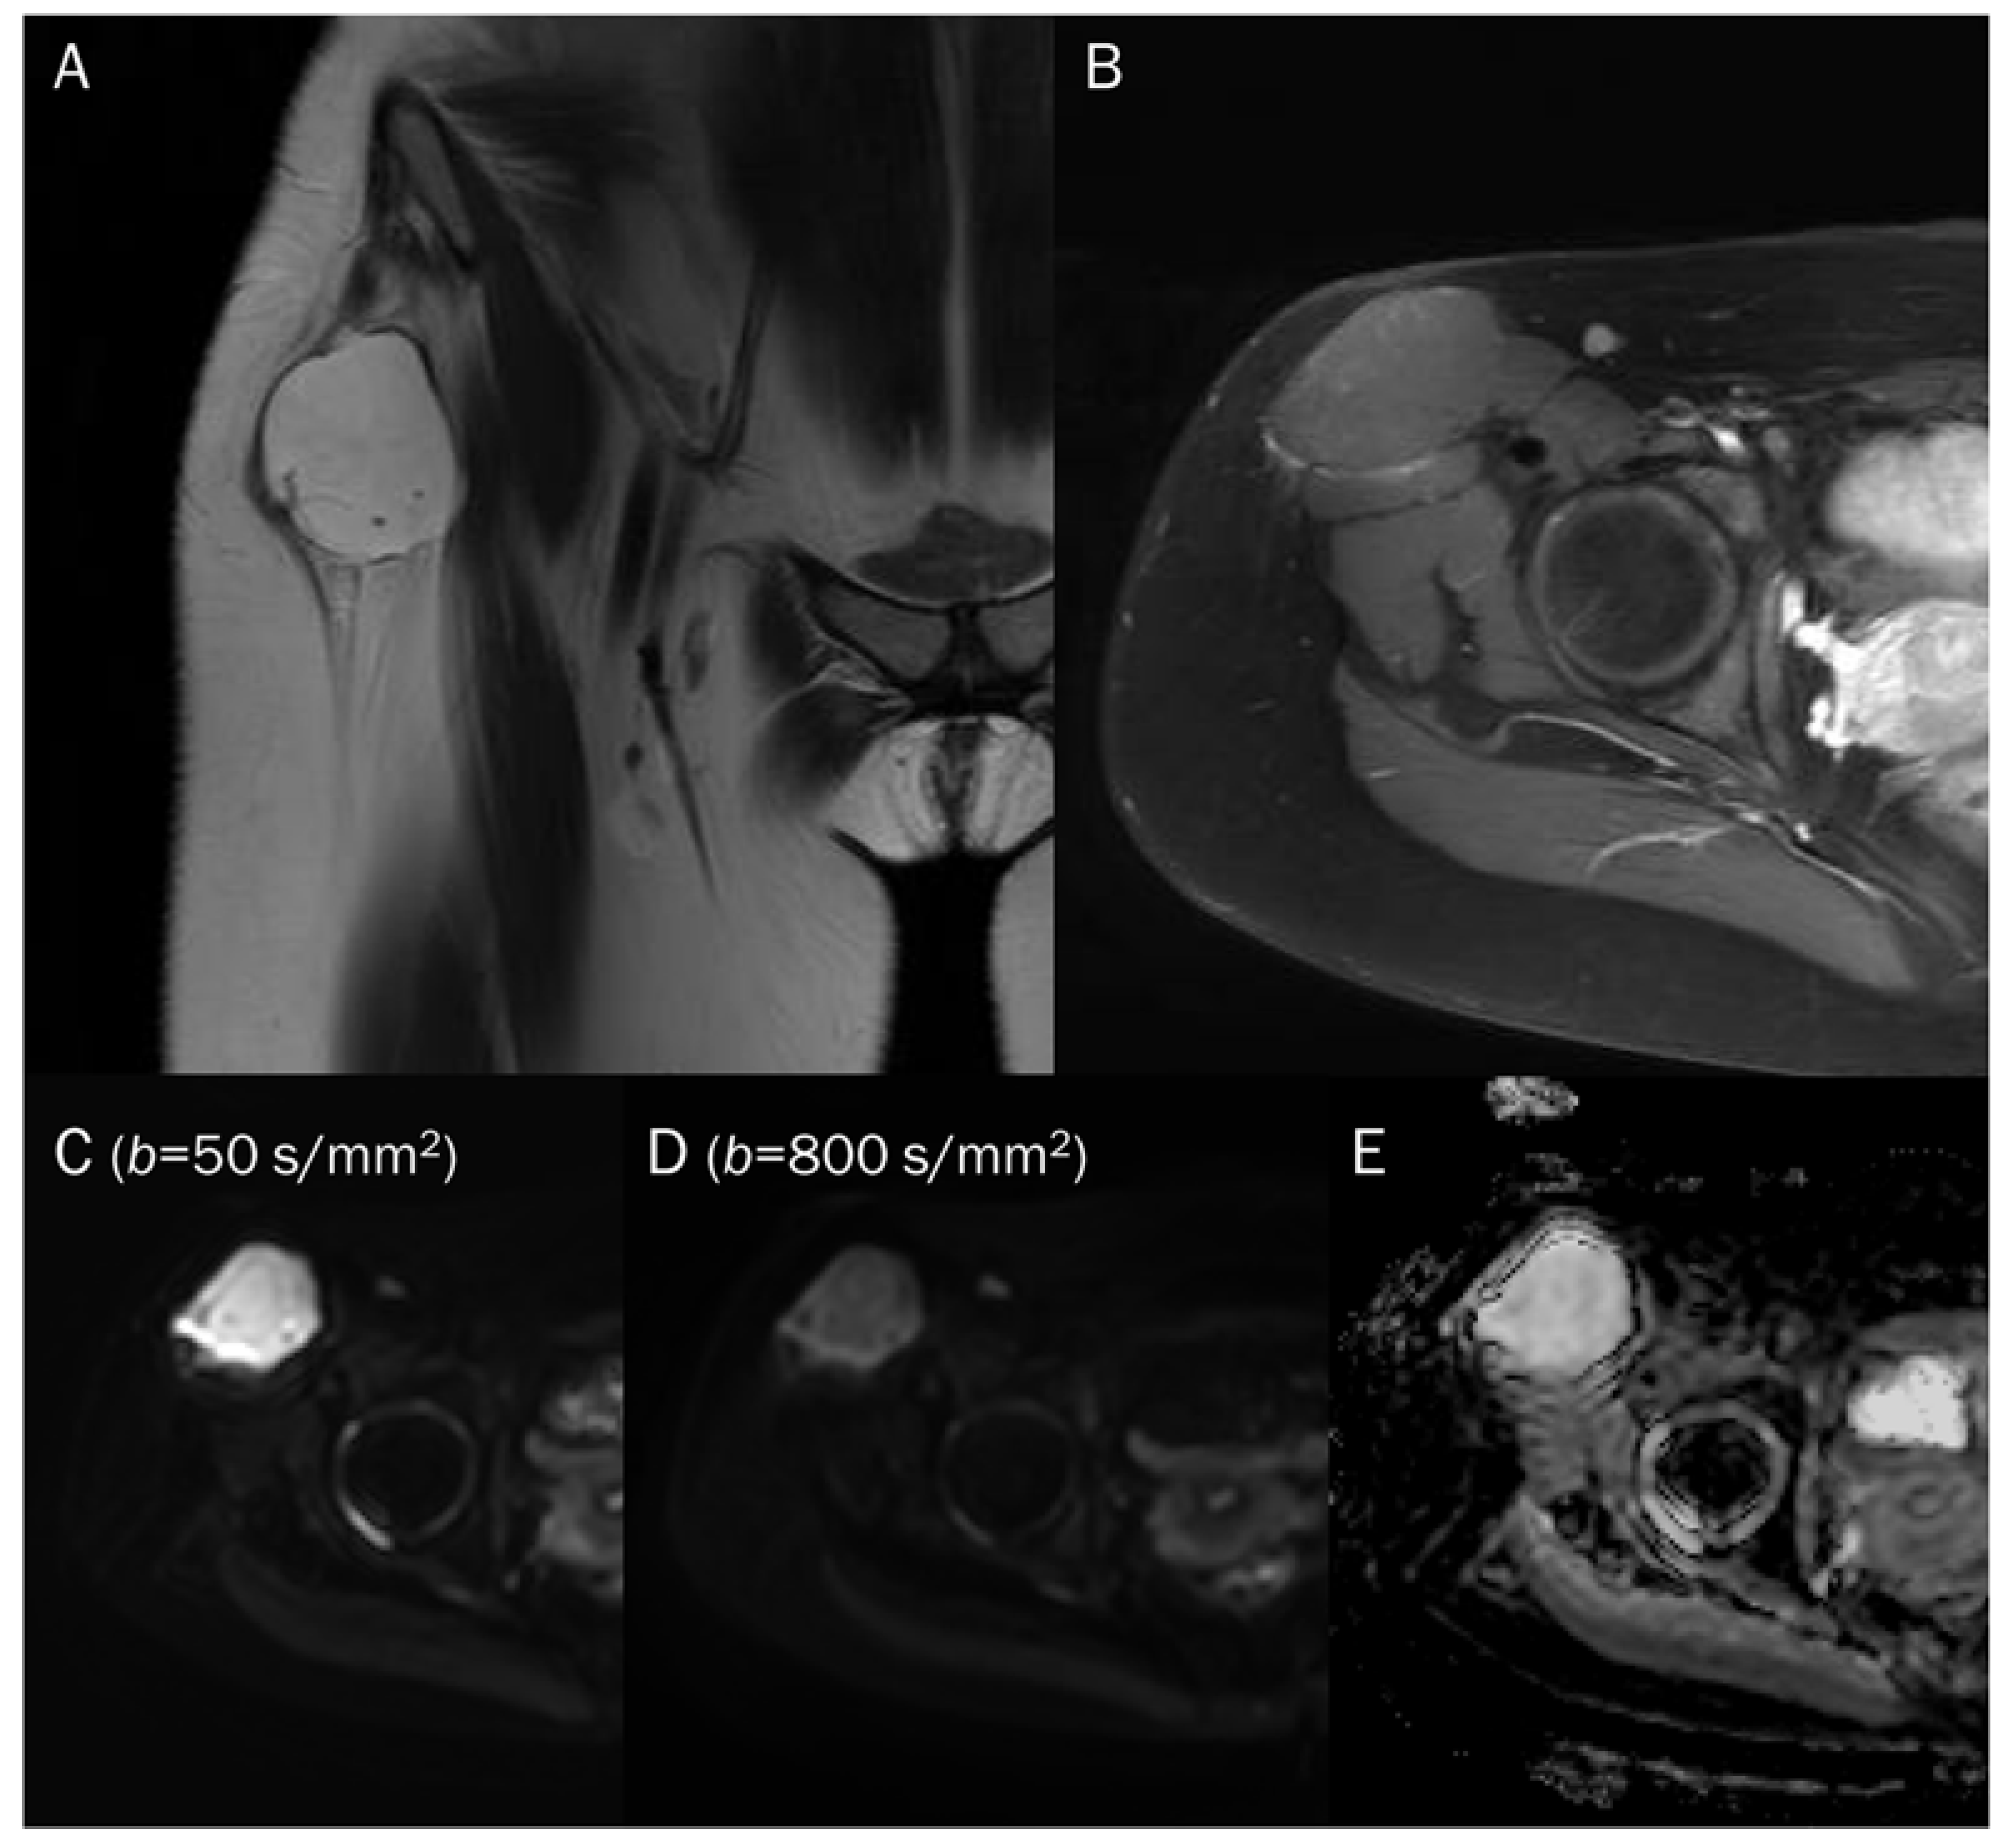

7.3. Benign Bone and Soft Tissue Tumors